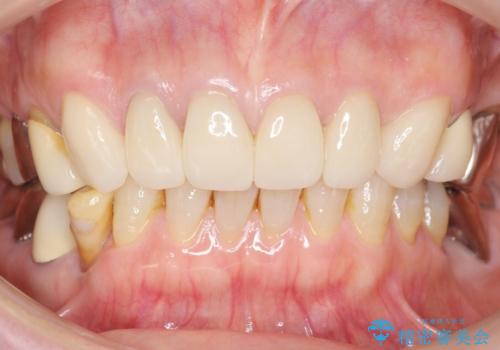

4年半前のクラウン装着時と変わらず、まるで天然歯のように自然に見えました。

患者様の良好なセルフケアと精密な適合の良いクラウンにより、歯肉の腫脹や退縮も認められませんでした。

エコノミーのオールセラミッククラウンに用いられるe-maxはニケイ酸リチウムガラスを主成分にしたセラミックです。

ガラスで出来ていることから非常に透明感があり、審美性と耐久性(強度はジルコニアの方が高い)を兼ね備えた材質です。

(強度 e-max:約400mPa、ジルコニア:900~1200mPa)

クラウンの種類:オールセラミッククラウン エコノミー